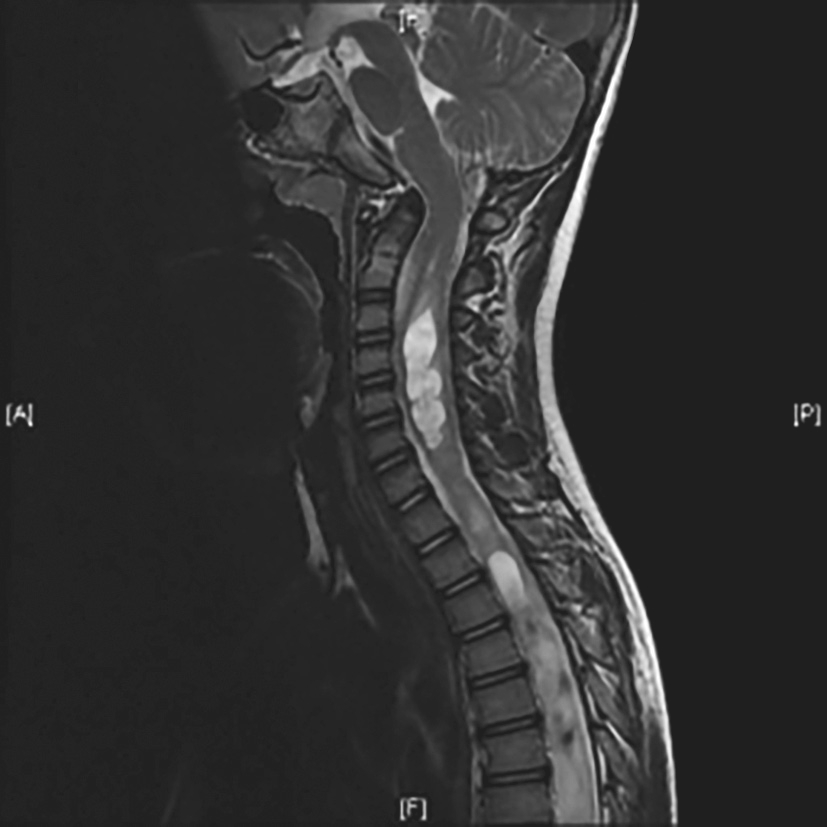

3)临床发现成人颅底凹陷时,多有明确的临床症状,需要手术治疗。BIb+O型(颅底凹陷,寰齿间距无增大,不合并脊髓空洞):此类患者如无明显临床症状,可随访观察;如来自前方的脑干受压严重,需经前方口咽入路切除上移突入枕骨大孔的骨质,Ⅰ期或Ⅱ期行枕颈固定融合术;如合并严重小脑扁桃体下疝,可经后路行显微枕下小脑扁桃体切除减压术,根据是否影响颅颈交界区稳定性,决定是否行寰枢或寰枕减压术。BIb+S型(颅底凹陷,寰齿间距无增大,合并脊髓空洞)(图4-4-4):需根据患者的临床症状与体征,结合CT、MRI及MRI电影成像进行综合评估,可行前路齿突切除骨性减压术。如果合并明显小脑扁桃体下疝和脊髓空洞,需要根据局部情况行后枕部硬脊膜下显微减压术。如果减压手术影响了颅颈交界区稳定性,需Ⅰ期行枕颈或寰枢固定融合术。

图4-4-4 BIb+S型颅底凹陷